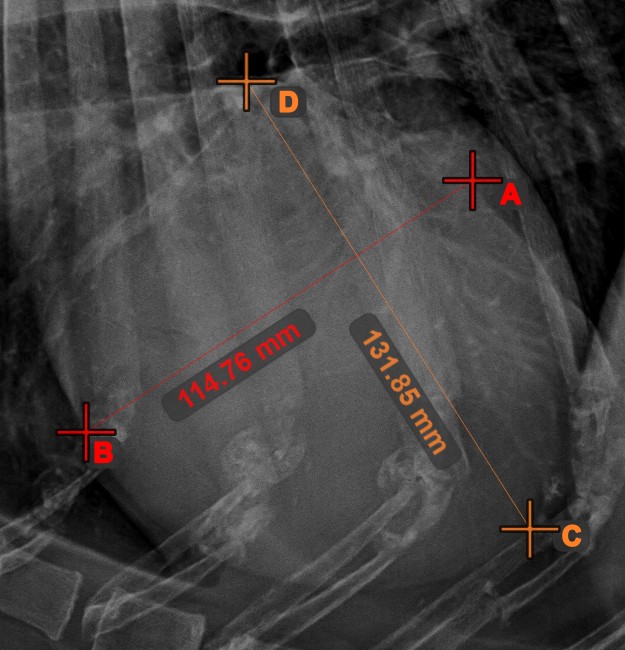

Linienmessung¶

Erstellen Sie eine Linienmessung, um den Abstand zwischen zwei Punkten mit hoher Genauigkeit zu berechnen.

Wählen Sie das Werkzeug Linienmessung

aus und weisen Sie es einer der verfügbaren Maustasten zu. Setzen Sie die Start- und Endpunkte in der Szene oder wählen Sie sie aus bereits vorhandenen Punkten im Bild aus. Der Abstand zwischen den beiden Punkten wird automatisch anhand der Standardkalibrierdaten oder der durch die Längenkalibrierung-Messung neu kalibrierten Daten berechnet.

Ändern Sie den Start- und Endpunkt mit dem Werkzeug Objekt auswählen/verschieben

. Der Abstand zwischen den beiden Punkten wird automatisch neu berechnet.

Mittlerer Punkt der Linie¶

Bestimmen und markieren Sie den Mittelpunkt einer neuen oder vorhandenen Linienmessung in der Szene mit dem Werkzeug Mittlerer Punkt der Linie

.

Wählen Sie das Werkzeug aus der linken Symbolleiste aus und weisen Sie es einer der verfügbaren Maustasten zu. Setzen Sie die Start- und Endpunkte in der Szene, wählen Sie sie aus bereits vorhandenen Punkten im Bild aus oder wählen Sie eine bereits gezeichnete Linie aus der Szene. Der Mittelpunkt der Linie wird automatisch berechnet und in der Szene platziert. Der Mittelpunkt jeder Linie wird stets mit dem Buchstaben C markiert.

Linienkreuzung¶

Lokalisieren und markieren Sie schnell und präzise den Schnittpunkt zwischen zwei vorhandenen Linien mit dem Werkzeug Linienkreuzung

Wählen Sie das Werkzeug aus der linken Symbolleiste aus und weisen Sie es einer der verfügbaren Maustasten zu. Wählen Sie zwei bereits in der Szene gezeichnete Linien aus, um die Messung abzuschließen. Der Schnittpunkt der Linien wird automatisch berechnet und in der Szene markiert. Der Schnittpunkt zweier Linien wird stets mit dem Buchstaben X markiert.

Informationen

Wenn sich zwei Linien nicht direkt schneiden, wird der Schnittpunkt ihrer verlängerten Projektionen in der Szene markiert.